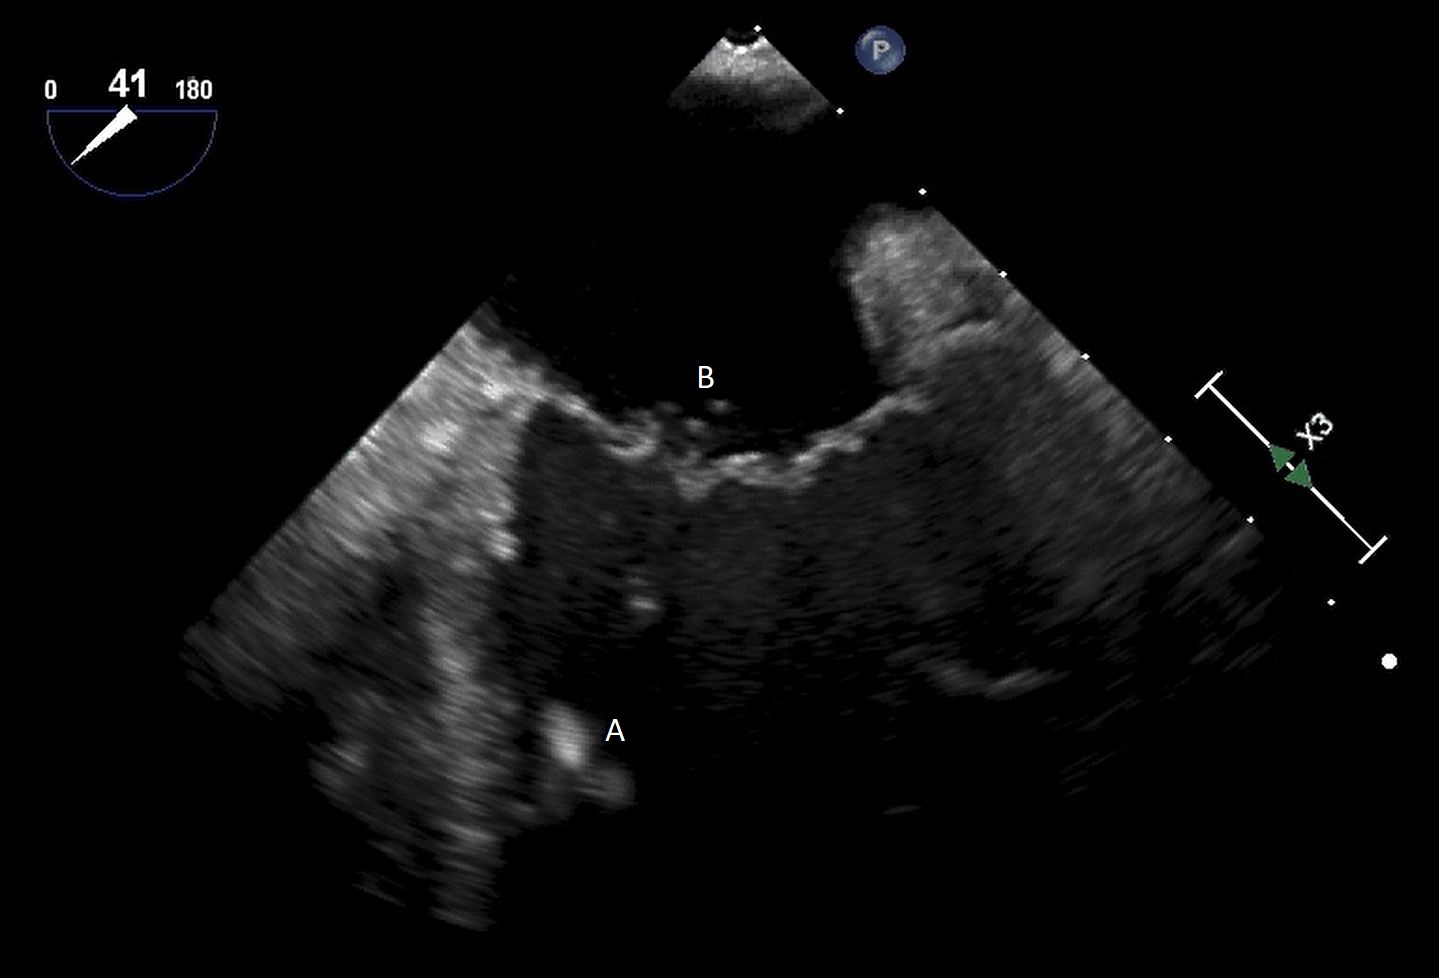

Both TTE and TEE can help with ideal positioning of the Impella (Figs. 5,6). The distance from the aortic valve to the Impella inlet should be measured. This should ideally be 3.5–4 cm for all Impella devices except for the Impella 5.5 for which it is 5 cm [15] (Fig. 7). The outlet should be 1.5–2 cm above the sinuses of Valsalva. The catheter should be angled towards the LV apex and away from the septum and mitral valve. The positioning of both the inlet in the LV cavity and the outlet above the aortic valve should be confirmed. Color flow doppler imaging can help confirm this positioning as a mosaic pattern will be visualized near the inlet and outlet ports on spectral doppler (Fig. 8). Real-time 3D echocardiography can also be used to help in visualizing Impella positioning relative to other anatomical structures (Fig. 9). After placement of the Impella, the aortic and mitral valves should be interrogated for any new or worsening regurgitation or dysfunction [16]. TEE can also help identify additional complications of Impella placement including pericardial effusion or LV free wall rupture [17].

Fig. 7.A parasternal long axis view on a transthoracic echocardiogram. The distance from the Impella inlet to the aortic valve is measured and noted to be 3.9 cm. (A) LV Cavity. (B) Impella. (C) Ascending aortic root.